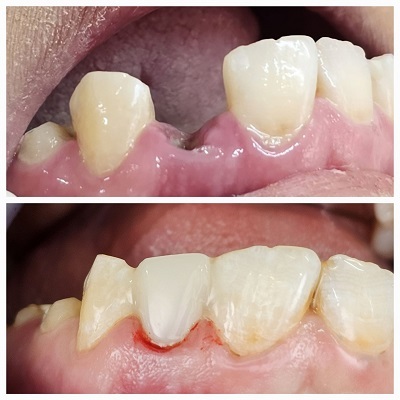

اگر که قصد انجام ایمپلنت دارید اما درگیر مشکلات لثه ای هستید بهتر است که قبل از انجام مراجعه به بهترین دکتر ایمپلنت در قم مشکل لثه خود را توسط بهترین دکتر لثه در قم درمان کنید و سپس کار ایمپلنت خود را شروع کنید.

دکتر علی رفیع درگاهی متخصص جراحی لثه می باشند انواع خدمات ایمپلنت و جایگذاری دندان از دست رفته را به بهترین نحو و با استفاده از متریال با کیفیت برای بیماران خود انجام می دهند. ایشان جزو بهترین دکتر ایمپلنت در قم که دارای شماره نظام پزشکی 68416 می باشند؛ گفتنی است که درصد بالایی از مراجعین از کار ایمپلنت و نیز دیگر خدمات دندانپزشکی ایشان رضایت دارند.